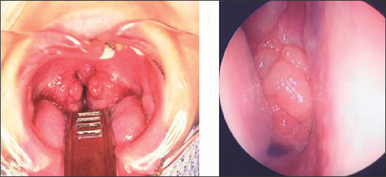

One of the most common cause of snoring in children is enlargement of tonsils and adenoid.

Adenotonsillectomy is indicated for this, and the procedure wont take long, around half to one hour. The recovery period usually takes 1 week.